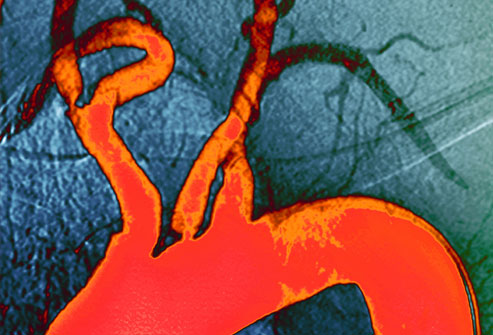

高胆固醇会导致能够阻塞动脉血管的斑块(橙色部分)。在斑块形成的很多年中你可能不会出现任何症状,并最终导致心脏病或中风。高血压、糖尿病和吸烟都会引起斑块淤积。斑块淤积被称为动脉粥样硬化。改变生活方式和药物治疗可以降低你的风险。